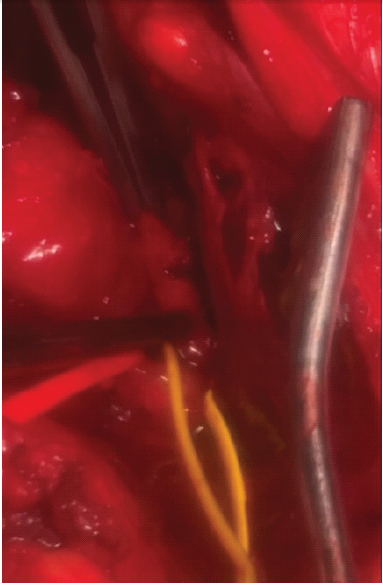

Figure 4: Intraoperative view following thrombectomy and primary repair in Case 2. Intraoperative close-up photograph demonstrating the repaired popliteal artery after thrombectomy and primary vascular repair performed in Case 2. The vessel is encircled with color-coded vessel loops to aid identification and maintain proximal and distal control. The lumen appears re-established, and arterial continuity is restored. The repair was performed after identification of a focal intraluminal thrombus causing complete loss of distal perfusion. This image was taken immediately following completion of the repair, before wound closure, confirming successful restoration of arterial patency.

Following repair, distal pulses returned and were confirmed on duplex imaging. The patient was placed on 325 mg aspirin for 2 weeks, followed by 81 mg for 10 additional weeks. He was monitored overnight with duplex ultrasound; the following morning, he remained stable and was discharged with intact neurovascular status. Notably, it was the presence of brisk bleeding during closure – rather than duplex findings alone – that prompted exploration. This case illustrates the importance of combining clinical signs with proper imaging in diagnosing arterial injury.